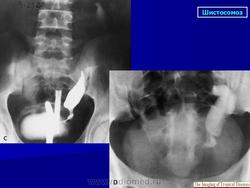

Бильгарциоз (Schistosomiasis) мочевого пузыря